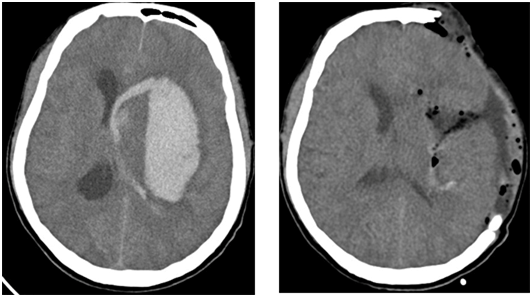

Đột quỵ xuất huyết não do vỡ mạch máu trong sọ gây ra.Đột quỵ xuất huyết não do vỡ mạch máu trong sọ gây ra.

Phẫu thuật giảm áp là phương pháp can thiệp ngoại khoa hữu hiệu và phổ biến.Phẫu thuật giảm áp là phương pháp can thiệp ngoại khoa hữu hiệu và phổ biến.